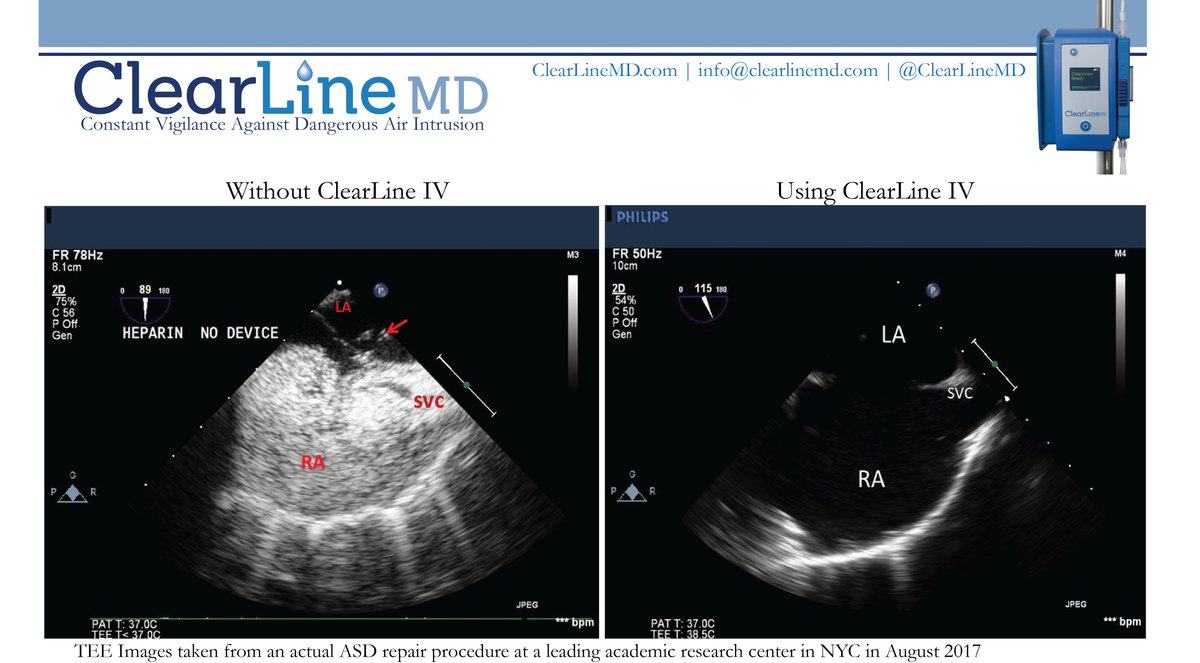

Developer of ClearLine IV, a new patient safety solution for Constant Vigilance Against Dangerous Air Burden & the catastrophic consequences of air embolism.